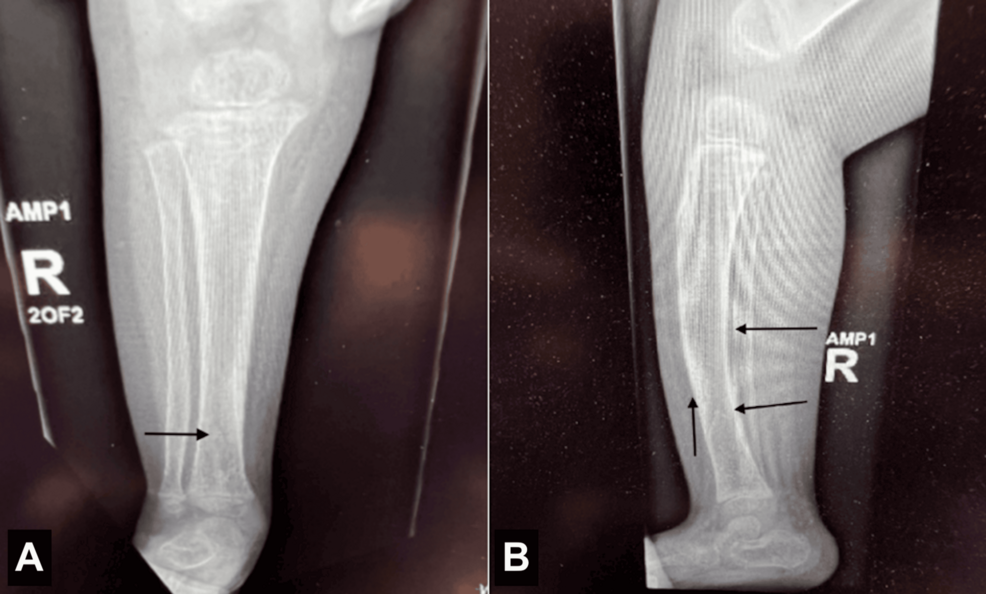

Subperiosteal Bone Formation: New bone formation occurs beneath the periosteum (the membrane covering bone), leading to thickening of the long bones, especially in the hands and feet. This is frequently enough painful.

2. Radiographic Imaging: X-rays reveal the subperiosteal bone formation and bone thickening. MRI can provide more detailed assessment of bone and soft tissue.